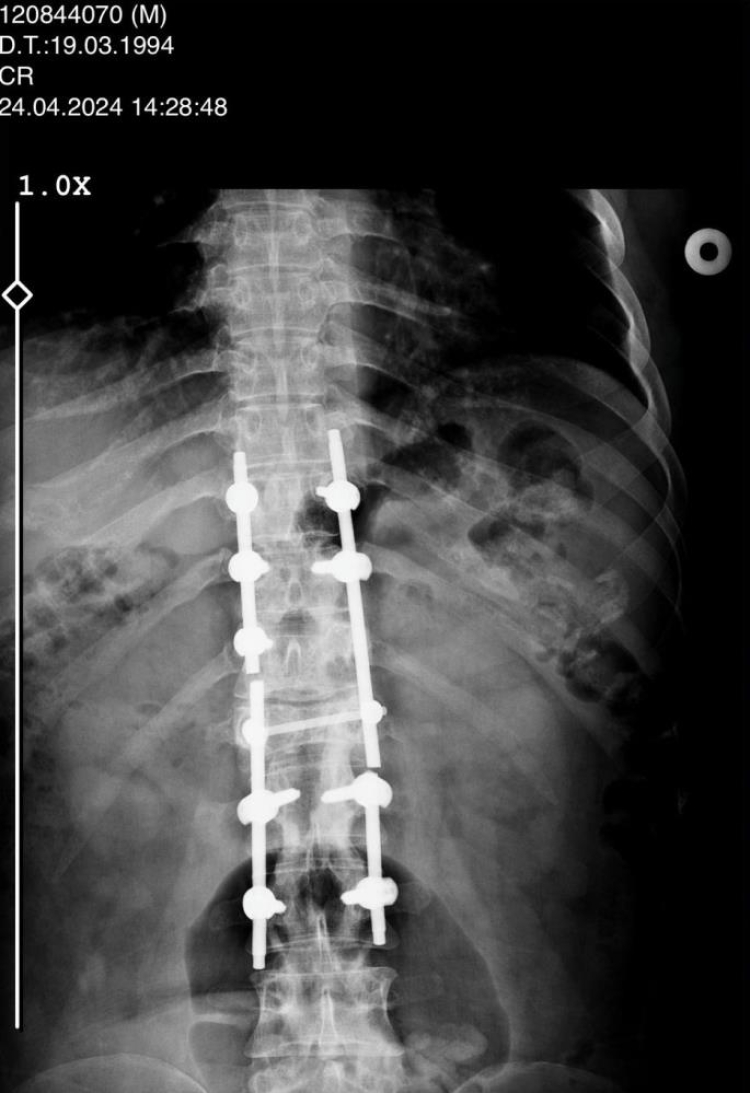

Konya'daki Afşar ve Bağbaşı Barajı arasındaki Mavi Tünel'in inşaatında Palet İnşaat bünyesinde ekskavatör operatörü olarak çalışan Sezgin Keşto (31), 1 Mart 2019'da, Cezmi Çelik'in (54) kullandığı beton mikserinin kaza yapması sonucu ağır yaralandı. Bu sırada sürücü Cezmi Çelik ise hayatını kaybetti. Araçtan çıkarıldıktan sonra Selçuk Üniversitesi Tıp Fakültesi Hastanesi'ne kaldırılan Keşto'nın omurgasının kırıldığı, omuriliğinin zedelendiği belirlendi. Geçirdiği ameliyatın ardından 3 gün yoğun bakımda kalan Keşto, 6 aylık tedaviden sonra taburcu edildi. Bir daha yürüyemeyeceğini öğrenen Keşto, Adana'daki ailesinin evine döndü.